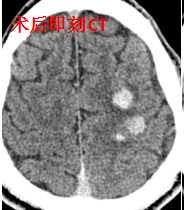

然而,就在手术结束的那一刻,术者敏锐地发现患者右上肢肌力突然由术前的3级(可抬离床面)降至0级(完全瘫痪)。虽然患者神志清楚、言语流利,但这一细微变化立即触发了抢救应急预案,复查头部CT显示:左侧额顶叶梗死区域出现脑出血转化——这正是高灌注综合征的典型表现!

面对这一突发状况,周元主任指导调整治疗方案,护理团队日夜守护,精准调控血压,患者和家人全力配合治疗!患者的病情逐步好转,最终康复出院,重获行走能力。